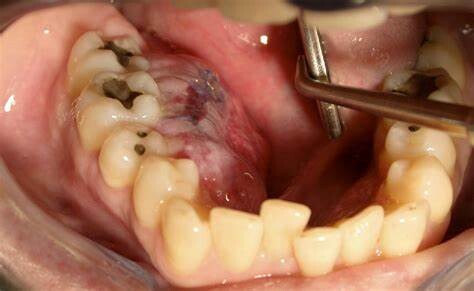

All About Osteosarcoma of the Jaw

Before discussing what osteosarcoma of the jaw is, it may be helpful to explain what sarcoma is in general. Sarcoma is a type of cancer that affects the body's connective tissues—the bones, cartilage, muscles, tendons, ligaments, fat, skin, nerves and blood vessels. This malignancy most commonly occurs in soft tissues, but it can also develop within the bones; when this happens, it’s referred to as "osteosarcoma" or "osteogenic sarcoma."

Although osteosarcoma can affect any bone in the body, it most commonly develops in the upper arm bone (humerus), the thigh bone (femur) and the shin bone (tibia). However, approximately 6% to 7% of osteosarcoma cases occur in the jawbone.

Jaw osteosarcoma symptoms

Individuals with osteosarcoma of the jaw most commonly complain of swelling (this is different than with long bone osteosarcoma, where the most common complaint is bone pain during activity). Other osteosarcoma of the jaw symptoms may include:

Ulcerations